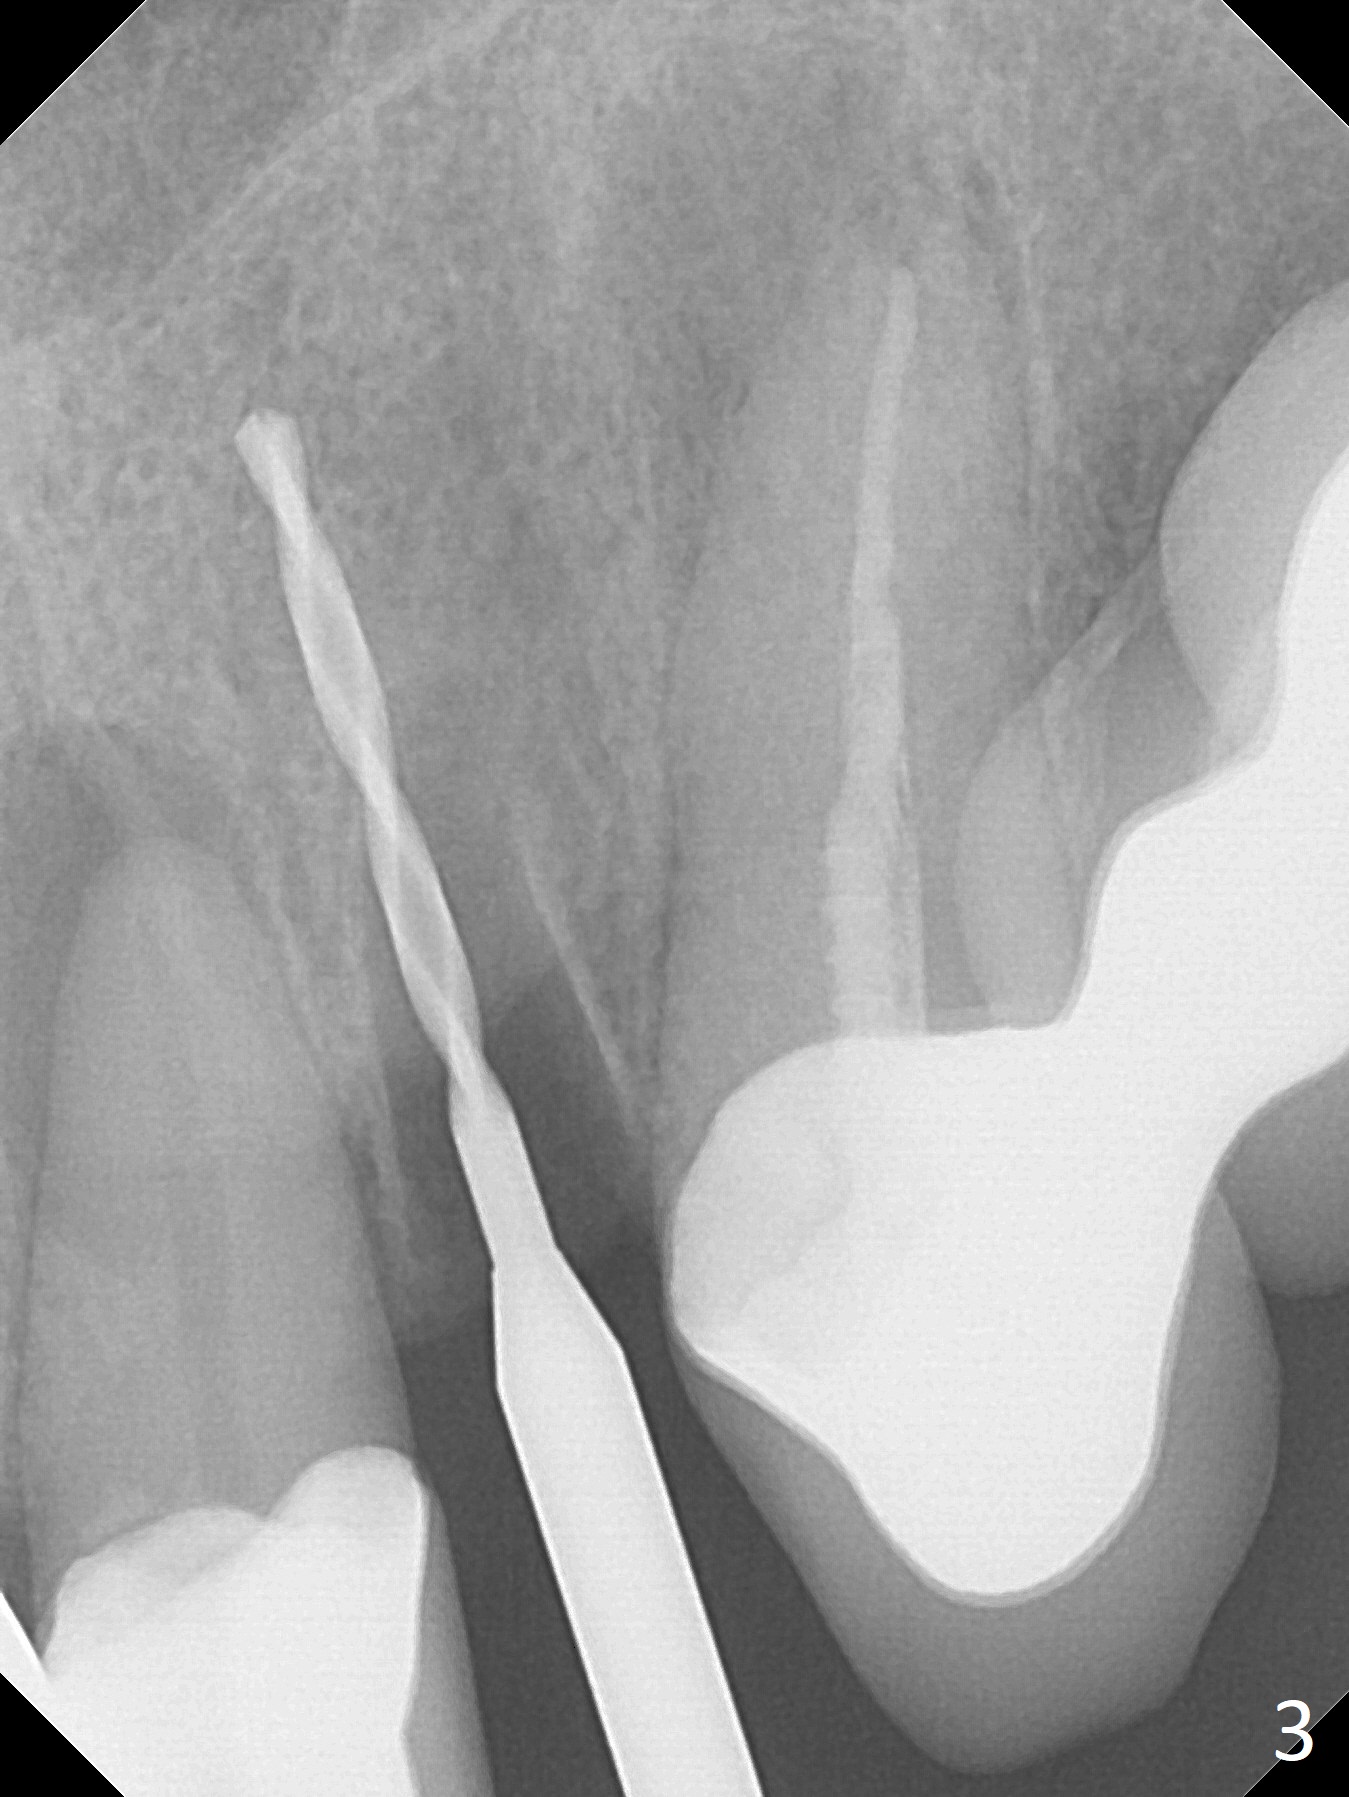

The tooth #10 fractures at the cervix, but is attached to the gingiva.  After extraction of the coronal portion of the tooth, the mesiodistal space palatally is found to be narrow (~4.7 mm, Fig.1).  It appears that a 1-piece implant is indicated because of the narrow mesiodistal space.  In fact the buccal plate of the socket is intact (Fig.2).  The initial osteotomy seems to be mesial (Fig.1) and is moved distal using Lindamann bur.  After sequential osteotomy, a 3x10 mm dummy implant is still mesial (Fig.4).  Following further distalization, a 3x14 mm implant is placed (Fig.5,6; <30 Ncm).  Vera Graft is placed in the remaining socket prior to provisional fabrication (Fig.6 *).  The socket outline disappears 7 months postop (Fig.7).  Panoramic X-ray is taken 1 year 3 month post cementation.